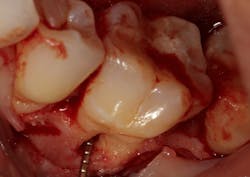

Figure 3: Tooth that would normally need to be extracted and replaced with an implant

The advent of laser technology, either as an adjunct to surgical therapy or as a monotherapy, has been met with mixed results in the literature.13 Recently, a new 9.3-micron CO2 laser (Solea from Convergent Dental) with the ability to cut both hard and soft tissue with efficiency was introduced to the dental market. This laser can penetrate deep defects with enough power to both thoroughly detoxify root surfaces and remove fibrous tissue, enhancing tissue repair (figure 2).14 The spot size of the focal laser beam can also be controlled to a range of .25 mm to 1.25 mm so that the beam can be directed into furcation entrances. This allows previously difficult furcal defects to be detoxified prior to regenerative therapy. Because of this enhanced ability to detoxify, this laser has been able to change the prognosis of once-hopeless teeth (figure 3) and allow for tissue regeneration (figure 4) instead of extraction.

Figure 4: Same tooth one year later after laser detoxification and periodontal regeneration with growth-stimulating factors